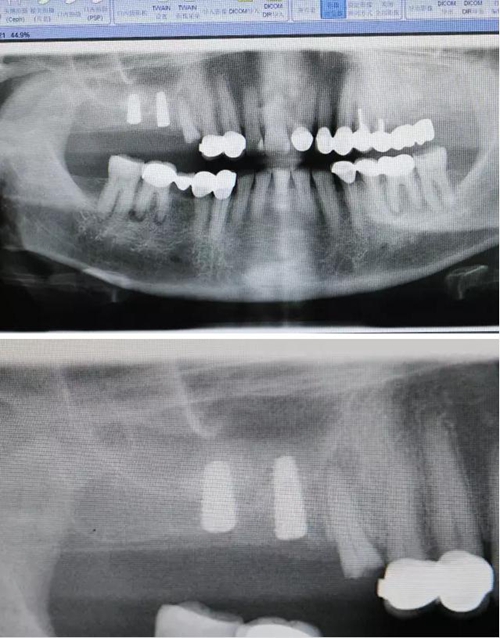

【病例分享】右上內(nèi)提+5冠延長(zhǎng)1 梁光強(qiáng)